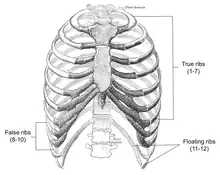

Slipping rib syndrome (SRS) is a condition in which the interchondral ligaments are weakened or disrupted and have increased laxity, causing the costal cartilage tips to subluxate (partially dislocate). This results in pain or discomfort due to pinched or irritated intercostal nerves, straining of the intercostal muscles, and inflammation. The condition affects the 8th, 9th, and 10th ribs, referred to as the false ribs, with the 10th rib most commonly affected.

A condition referred to as twelfth rib syndrome is similar to slipping rib syndrome; however, it affects the floating ribs (11-12) which do not have any attachments to the sternum. Some researchers classify slipping rib syndrome and twelfth rib syndrome into a group referred to as painful rib syndrome, others classify twelfth rib syndrome as a subtype of slipping rib syndrome, and some considering the two to be separate conditions altogether. The two disorders have different presentation and diagnostic criteria, such that a diagnosis for twelfth rib syndrome does not include the hooking maneuver and typically presents as lower back, abdominal, and groin pain.[15]